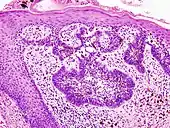

Main types of staining seen on H&E stain.

Examples of H&E stained tissues